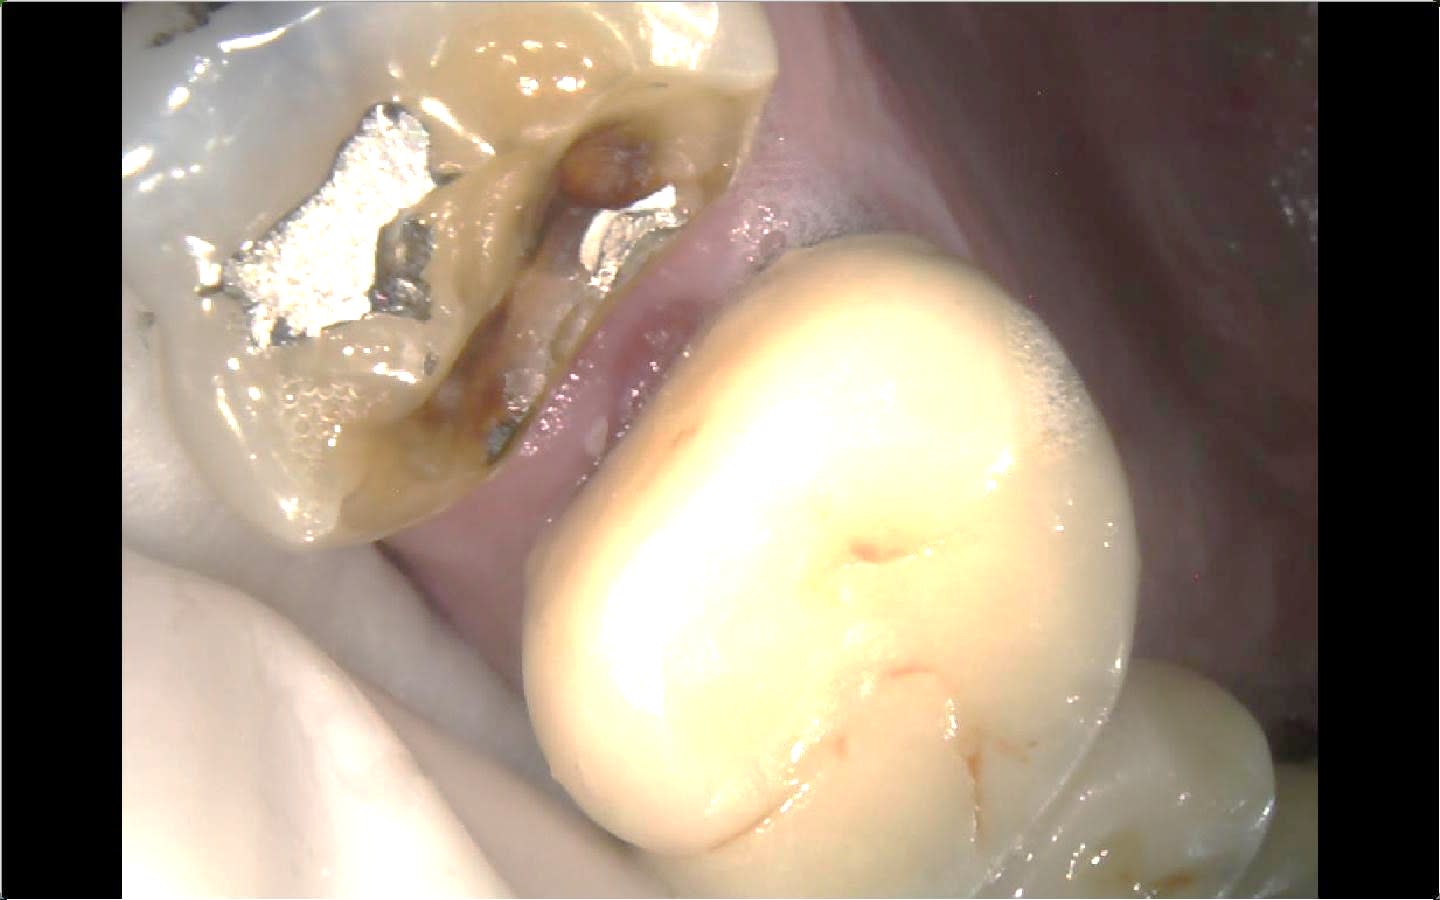

du coup avec le fil + teflon , tu le mets AVANT taille , ce qui te permet de repousser toute la papille apicalement . et contrairement à un fil tu ne rentres pas dans le sulcus , et donc ça ne saigne pas .( même quand tu l enlèves )

et de peu que tu l'esquiches bien avec un fouloir , il est tellement cohésif que tu peux même tailler dedans à la fraise diamant , il ne part pas en charpie .

tu peux donc te descendre le trottoir de la box tranquille , mais alors tranquille , hein .

aller coup de folie , après tu peux même te faire une remontée de marge dans la foulée .

Fil2 b5v6tr - Eugenol